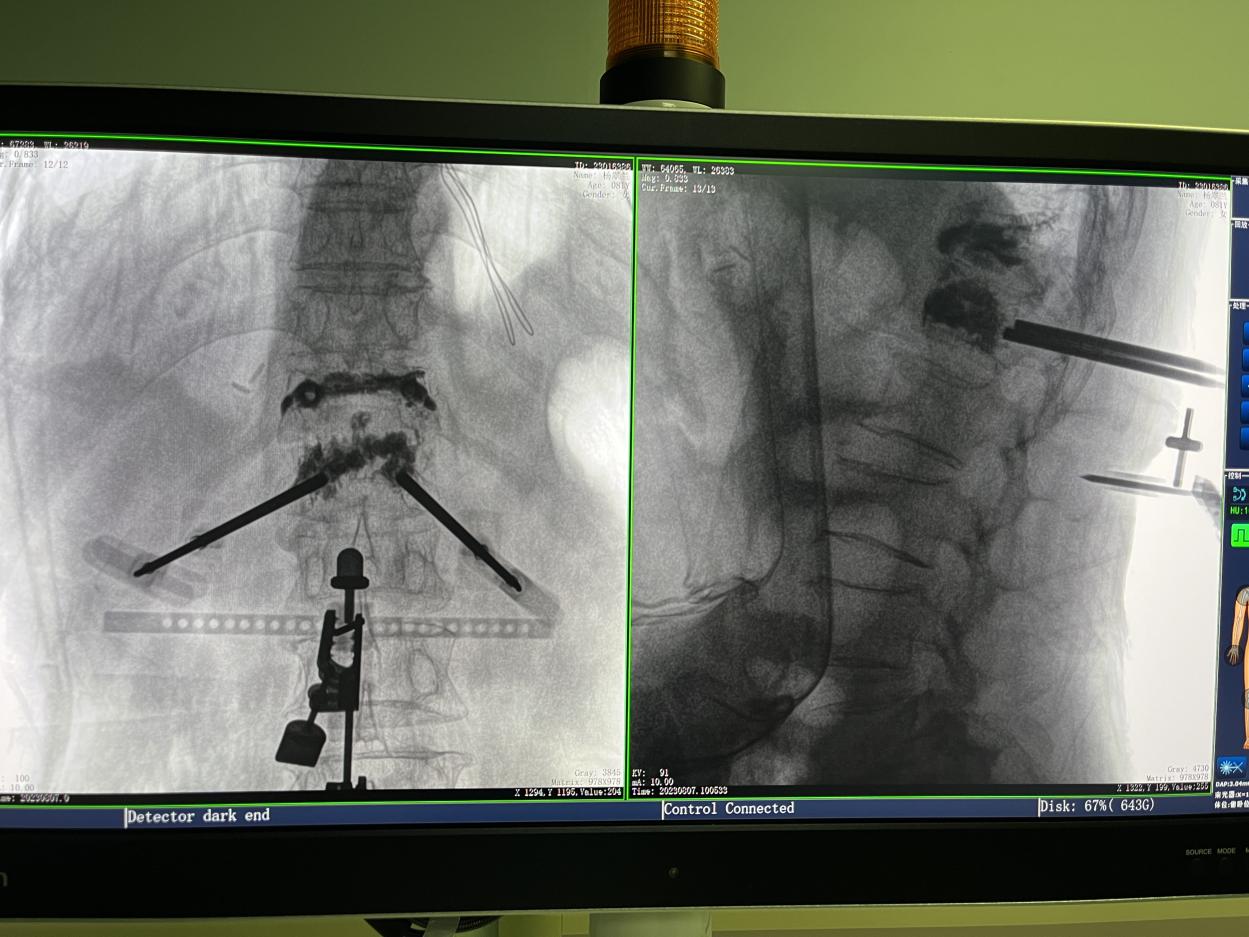

传统的开放式手术需暴露手术可见视野,以便医生获得更多的判断信息,手术创口大,术后恢复时间长。而在骨科机器人辅助的微创手术中,手术创口仅为1~2厘米左右的小切口,创伤小、恢复快。

骨科机器人手术-术后影像